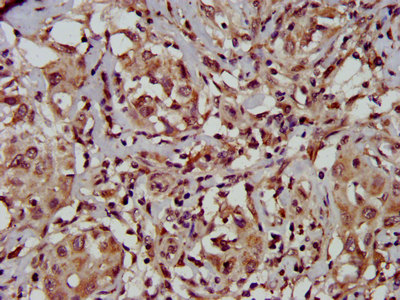

IHC image of CSB-PA023420LA01HU diluted at 1:500 and staining in paraffin-embedded human pancreatic cancer performed on a Leica BondTM system. After dewaxing and hydration, antigen retrieval was mediated by high pressure in a citrate buffer (pH 6.0). Section was blocked with 10% normal goat serum 30min at RT. Then primary antibody (1% BSA) was incubated at 4°C overnight. The primary is detected by a biotinylated secondary antibody and visualized using an HRP conjugated SP system.